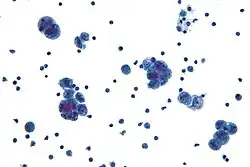

Diagnosis of ovarian cancer starts with a physical examination (including a pelvic examination), a blood test (for CA-125 and sometimes other markers), and transvaginal ultrasound.[26][58] Sometimes a rectovaginal examination is used to help plan a surgery.[29] The diagnosis must be confirmed with surgery to inspect the abdominal cavity, take biopsies (tissue samples for microscopic analysis), and look for cancer cells in the abdominal fluid. This helps to determine if an ovarian mass is benign or malignant.[26]

To definitively diagnose ovarian cancer, a surgical procedure to inspect the abdomen is required. This can be an open procedure (laparotomy, incision through the abdominal wall) or keyhole surgery (laparoscopy). During this procedure, suspicious tissue is removed and sent for microscopic analysis. Usually, this includes a unilateral salpingo-oophorectomy, removal of a single affected ovary and Fallopian tube. Fluid from the abdominal cavity can also be analyzed for cancerous cells. If cancer is found, this procedure can also be used to determine the extent of its spread (which is a form of tumor staging).[26]